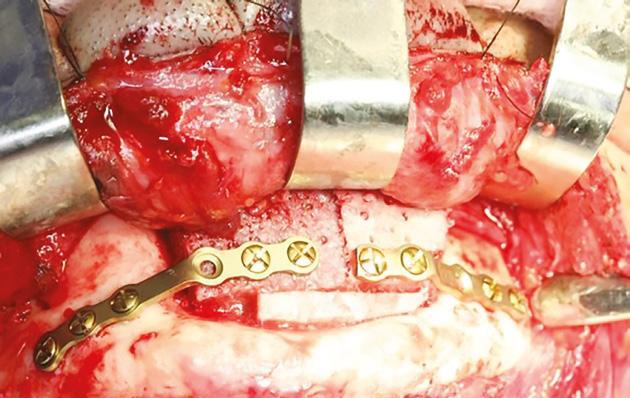

Paciente do sexo masculino, 22 anos de idade, procurou o Serviço de Cirurgia e Traumatologia Bucomaxilofacial do Hospital das Clínicas da Universidade Federal de Minas Gerais, para avaliação de lesão assintomática em mandíbula. Ele relatou ausência de sintomatologia álgica, parestesia, hipoestesia ou disestesia, e não apresentava comorbidades. Ao exame físico extrabucal e intrabucal, não foram detectadas alterações dignas de nota (Fig. 1A). Entretanto, o exame tomográfico revelou extensa imagem hipodensa na região de sínfise e corpo esquerdo de mandíbula, multiloculada, com aspecto de destruição e expansão óssea, e associada aos dentes 31, 32, 33, 34, 35 e 41 (Fig. 1B). Uma biópsia incisional confirmou a hipótese diagnóstica de AM convencional (Fig. 1C). Por meio de um acesso cirúrgico intrabucal e sob anestesia geral, o tumor foi removido através de uma ressecção marginal mínima da mandíbula, com margem de segurança óssea variando entre 5 e 10 mm, preservando a borda inferior mandibular, e exodontia dos elementos associados, além do dente 42 (Fig. 1D). Terapias coadjuvantes, como ostectomia periférica em toda extensão da lesão e aplicação de solução de Carnoy (3ml de clorofórmio, 6ml de álcool absoluto, 1ml de ácido glacial acético e 1g de clorito férrico), durante 5 minutos, foram realizadas em toda loja cirúrgica. Após um período de 4 anos de controle pós-operatório, com consultas trimestrais no primeiro ano, semestrais no segundo, e anuais a partir do terceiro ano, não foram observados, em exames clínicos e de imagem, sinais de recidiva da lesão. O paciente foi, então, submetido a um procedimento de reconstrução mandibular, que consistiu na colocação, por meio de um acesso cirúrgico extrabucal (submentoniano), de um enxerto livre autógeno de crista ilíaca, fixado com placas de titânio do sistema 2.0 (Fig. 2). Transcorridos cinco meses da enxertia, a região foi reabilitada por meio de uma prótese dentária implantossuportada, utilizando-se quatro implantes: três implantes plataforma Cone Morse de 3,75 mm de diâmetro por 13 mm de comprimento, na área enxertada; e um implante na posição de molares, plataforma Cone Morse, de 5 mm de diâmetro e 11 mm de comprimento (Fig. 3A e 3B). Após nove anos da cirurgia para a ressecção tumoral, observou-se ausência de sinais de recidiva e o paciente encontrava-se satisfeito com o resultado do tratamento (Fig. 3B e 3C).

Figura 2: Reconstrução do defeito cirúrgico com enxerto livre e autógeno de crista ilíaca, 4 anos após a ressecção do tumor.